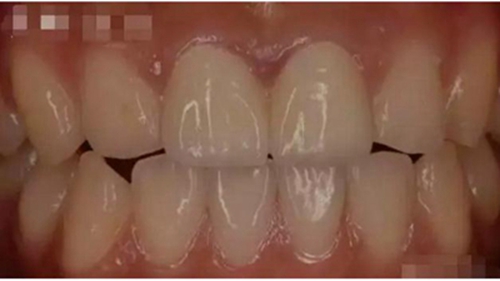

這幾天,一張照片刷爆了牙醫(yī)朋友圈

對(duì)這張照片,有牙醫(yī)評(píng)論如下:

口內(nèi)有金屬烤瓷牙做核磁共振,CT,以烤瓷牙為中心呈現(xiàn)放射狀影像,無法看清周圍組織,影響臨床診斷,建議條件允許的朋友還是選擇二氧化鋯全瓷冠修復(fù),以免帶來不必要的麻煩!

2.jpg

3,美學(xué)效果優(yōu)異

成功的全瓷牙修復(fù)外表逼真美觀、堅(jiān)固耐磨,色澤近似于天然牙,生物相容性良好,不刺激口腔組織,容易清潔,既能回復(fù)牙齒的功能,又有美容的作用。最主要的是全瓷牙具有良好的透明性和折光性,不會(huì)在牙頸部出現(xiàn)黑線,使牙頸部也能達(dá)到良好的美觀效果,這是一般烤瓷牙無法比擬的。